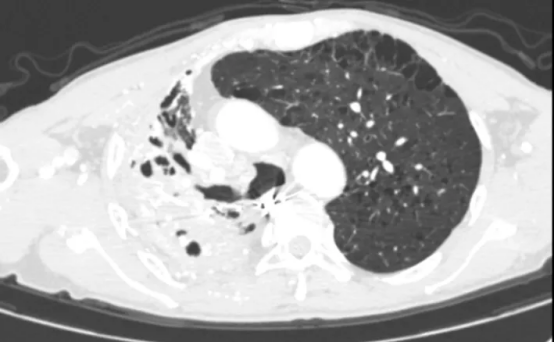

术后影像

术后,患者转入重症一科,在孙万里副主任医师的精细化治疗与护理下,患者接连闯过感染、出血、呼吸功能支持等重重难关。4天后病情趋于稳定,转回胸外二科继续康复。在医护人员的悉心照料下,患者康复出院。